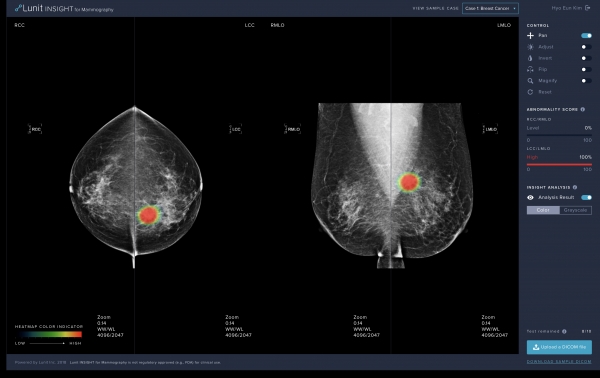

해당 제품은 인공지능 기술을 기반으로 설계된 유방촬영영상 판독보조 소프트웨어로, 유방암 의심 부위와 의심 정도를 색상 등으로 표기, 의사의 정확한 진단을 돕는다.

루닛 인사이트 MMG는 5만여 명의 유방암 케이스를 포함한 20만여 명의 유방촬영영상을 딥러닝 학습에 활용해 악성 종양만을 검출해낸다.

루닛 김효은 이사는 “특히 기존 컴퓨터 보조 진단 소프트웨어에서 문제가 됐던 높은 위양성률을 극복하기 위해 악성과 양성 종양을 높은 정확도로 구분할 수 있도록 개발됐다”며 “식약처 확증 임상 시험을 통해 영상의학과 전문의의 판독 정확도를 크게 향상시키는 것으로 확인됐다”고 말했다.